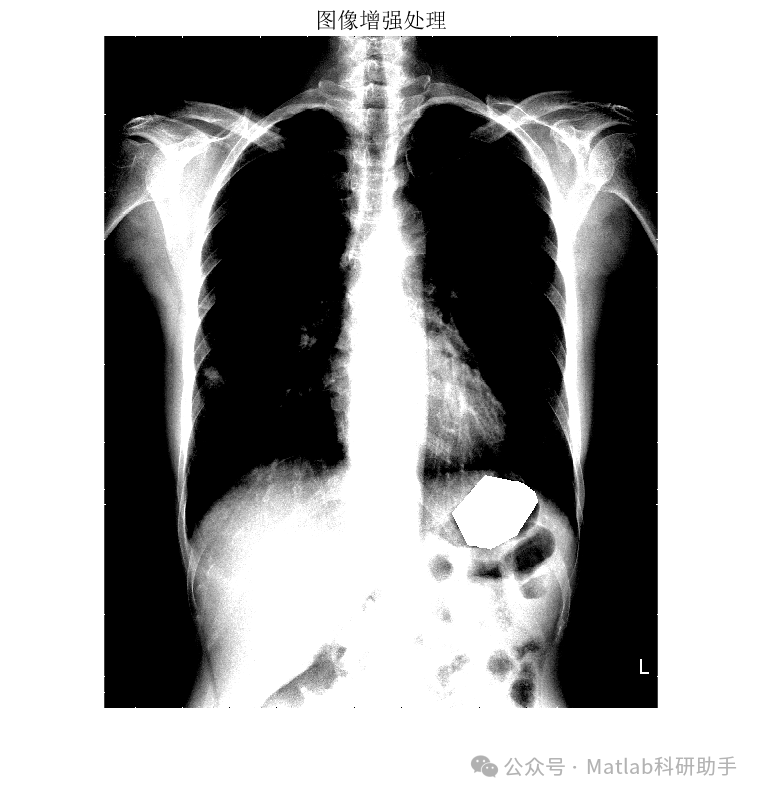

胸片分割作为计算机辅助诊断系统中的关键环节,旨在从胸片图像中精确提取肺部区域,为后续疾病诊断和定量分析提供基础。传统的胸片分割方法往往依赖于人工设计的特征或复杂的图像处理流程,鲁棒性较差。近年来,深度学习凭借其强大的特征学习能力,为胸片分割带来了新的突破。

基于最小误差法的胸片分割系统,通常采用深度学习模型,如U-Net或其变体,作为核心分割引擎。该模型通过大量标注数据进行训练,学习从胸片图像到肺部区域掩膜的映射关系。其核心思想是最小化模型预测的分割结果与真实标注之间的误差,从而实现准确的分割。

⛳️ 运行结果